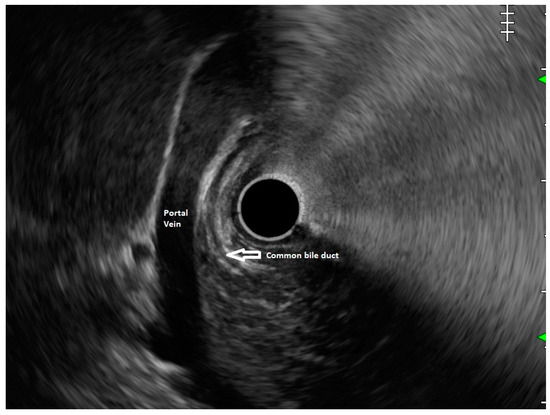

5. Pancreas Divisum

6. Endoscopic Ultrasound Features of Pancreas Divisum: Radial and Linear EUS